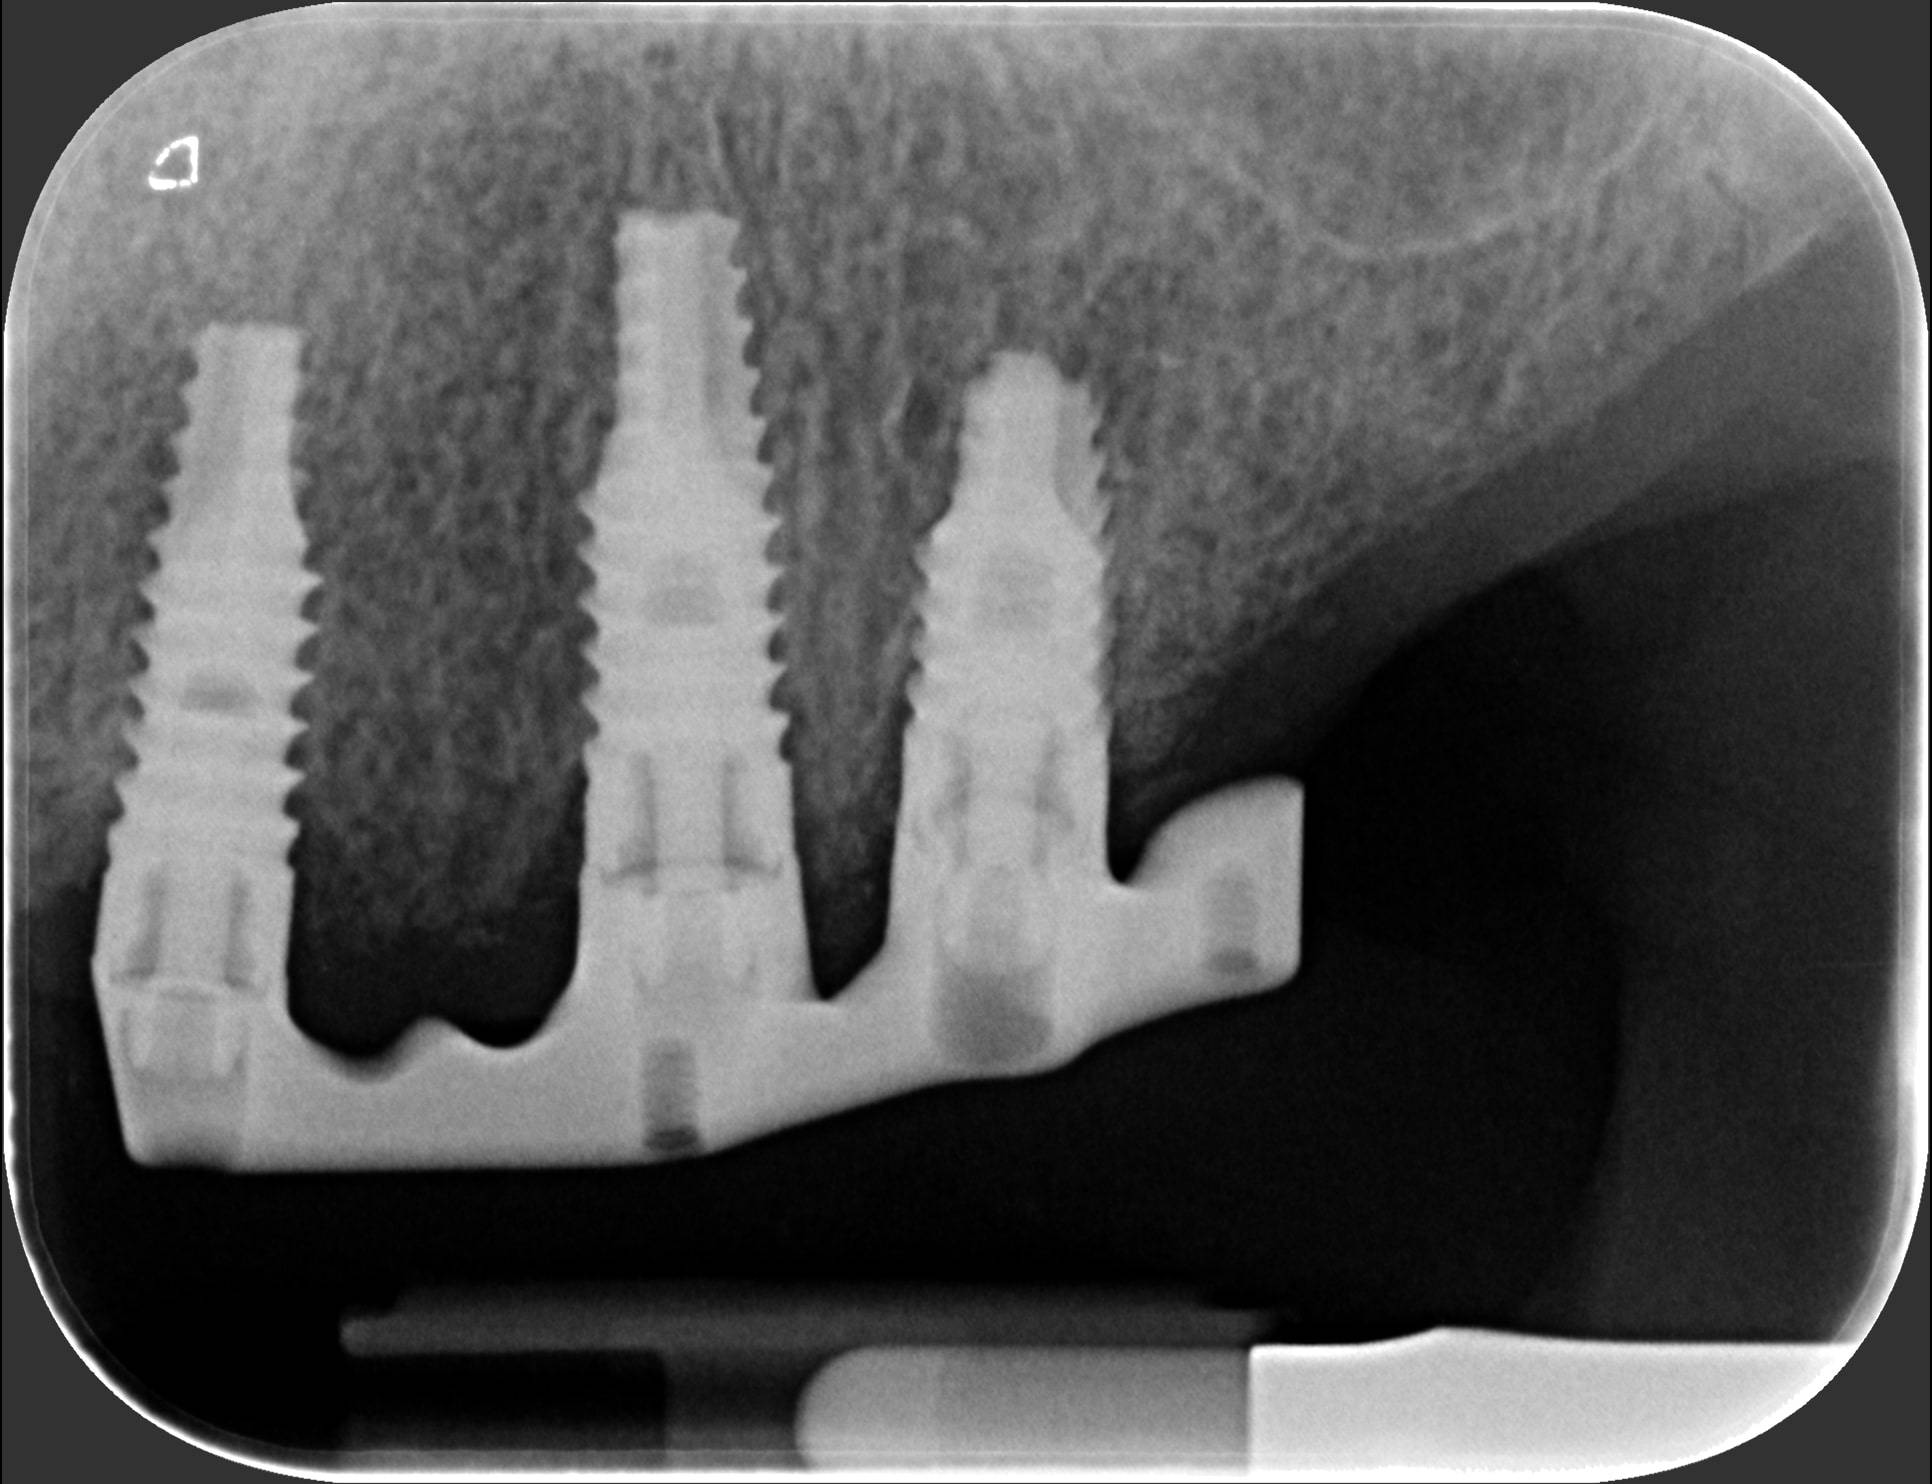

In questi casi la migliore soluzione, dopo aver estratto i quattro denti traballanti, è programmare un numero di impianti sufficiente ad eseguire una protesi fissa. Poi, una volta avvenuta l’osteointegrazione, si prende l’impronta di precisione; un laboratorio specializzato crea successivamente delle strutture metalliche in titanio (quelle che noi dentisti chiamiamo “primarie”), che poi vengono avvitate sugli impianti solidarizzandoli tra loro.

Puoi vedere le radiografie delle due barre avvitate nelle successive due foto. Sopra queste barre viene quindi avvitata l’ampia struttura metallica (che chiamiamo “secondaria”), che porta i denti artificiali di tutta l’arcata. E così, la signora si è ritrovata tutti denti fissi con cui può ridere, masticare e tornare ad una vita finalmente normale. Adesso confronta l’ultima foto con la prima e capirai come l’implantologia può cambiarti la vita in meglio. Questo è ciò a cui miriamo ogni giorno nello Studio dentistico del dott. Fabio Ballestrasse a Besana Brianza e se sei di Barzanò adesso sai a chi rivolgerti.